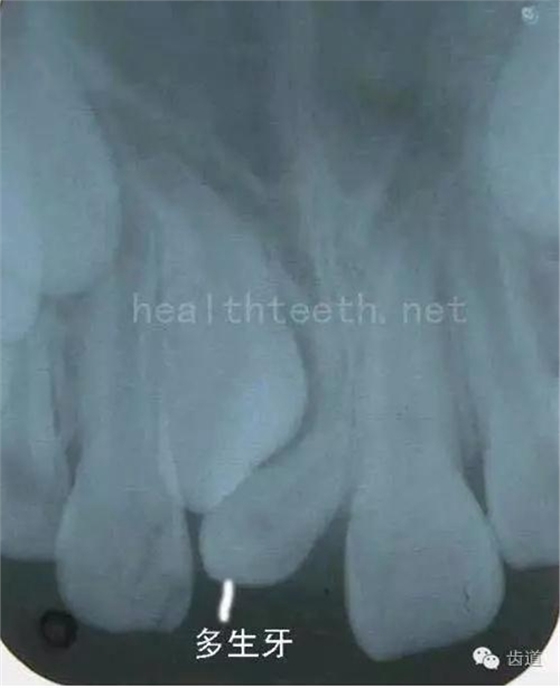

舌緣創(chuàng)傷性潰瘍